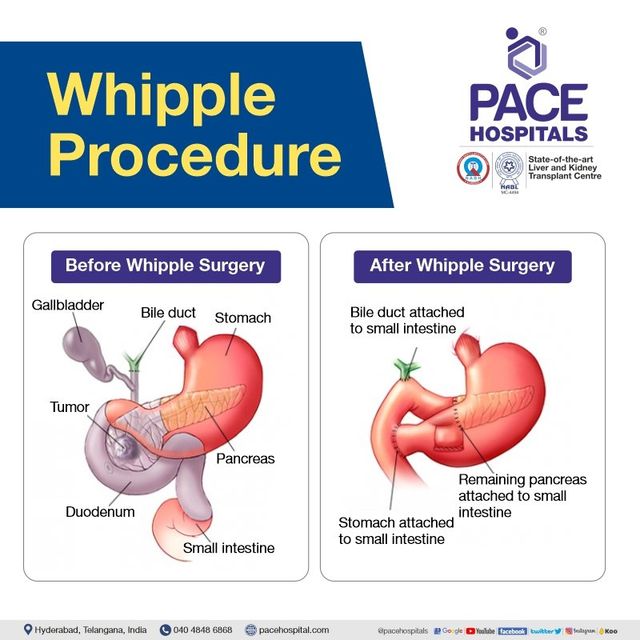

Whipple Procedure Steps Complications Purpose And More 40 OFF

Whipple Procedure Anatomy

Whipple Procedure Diagram

Whipple Procedure Diagram